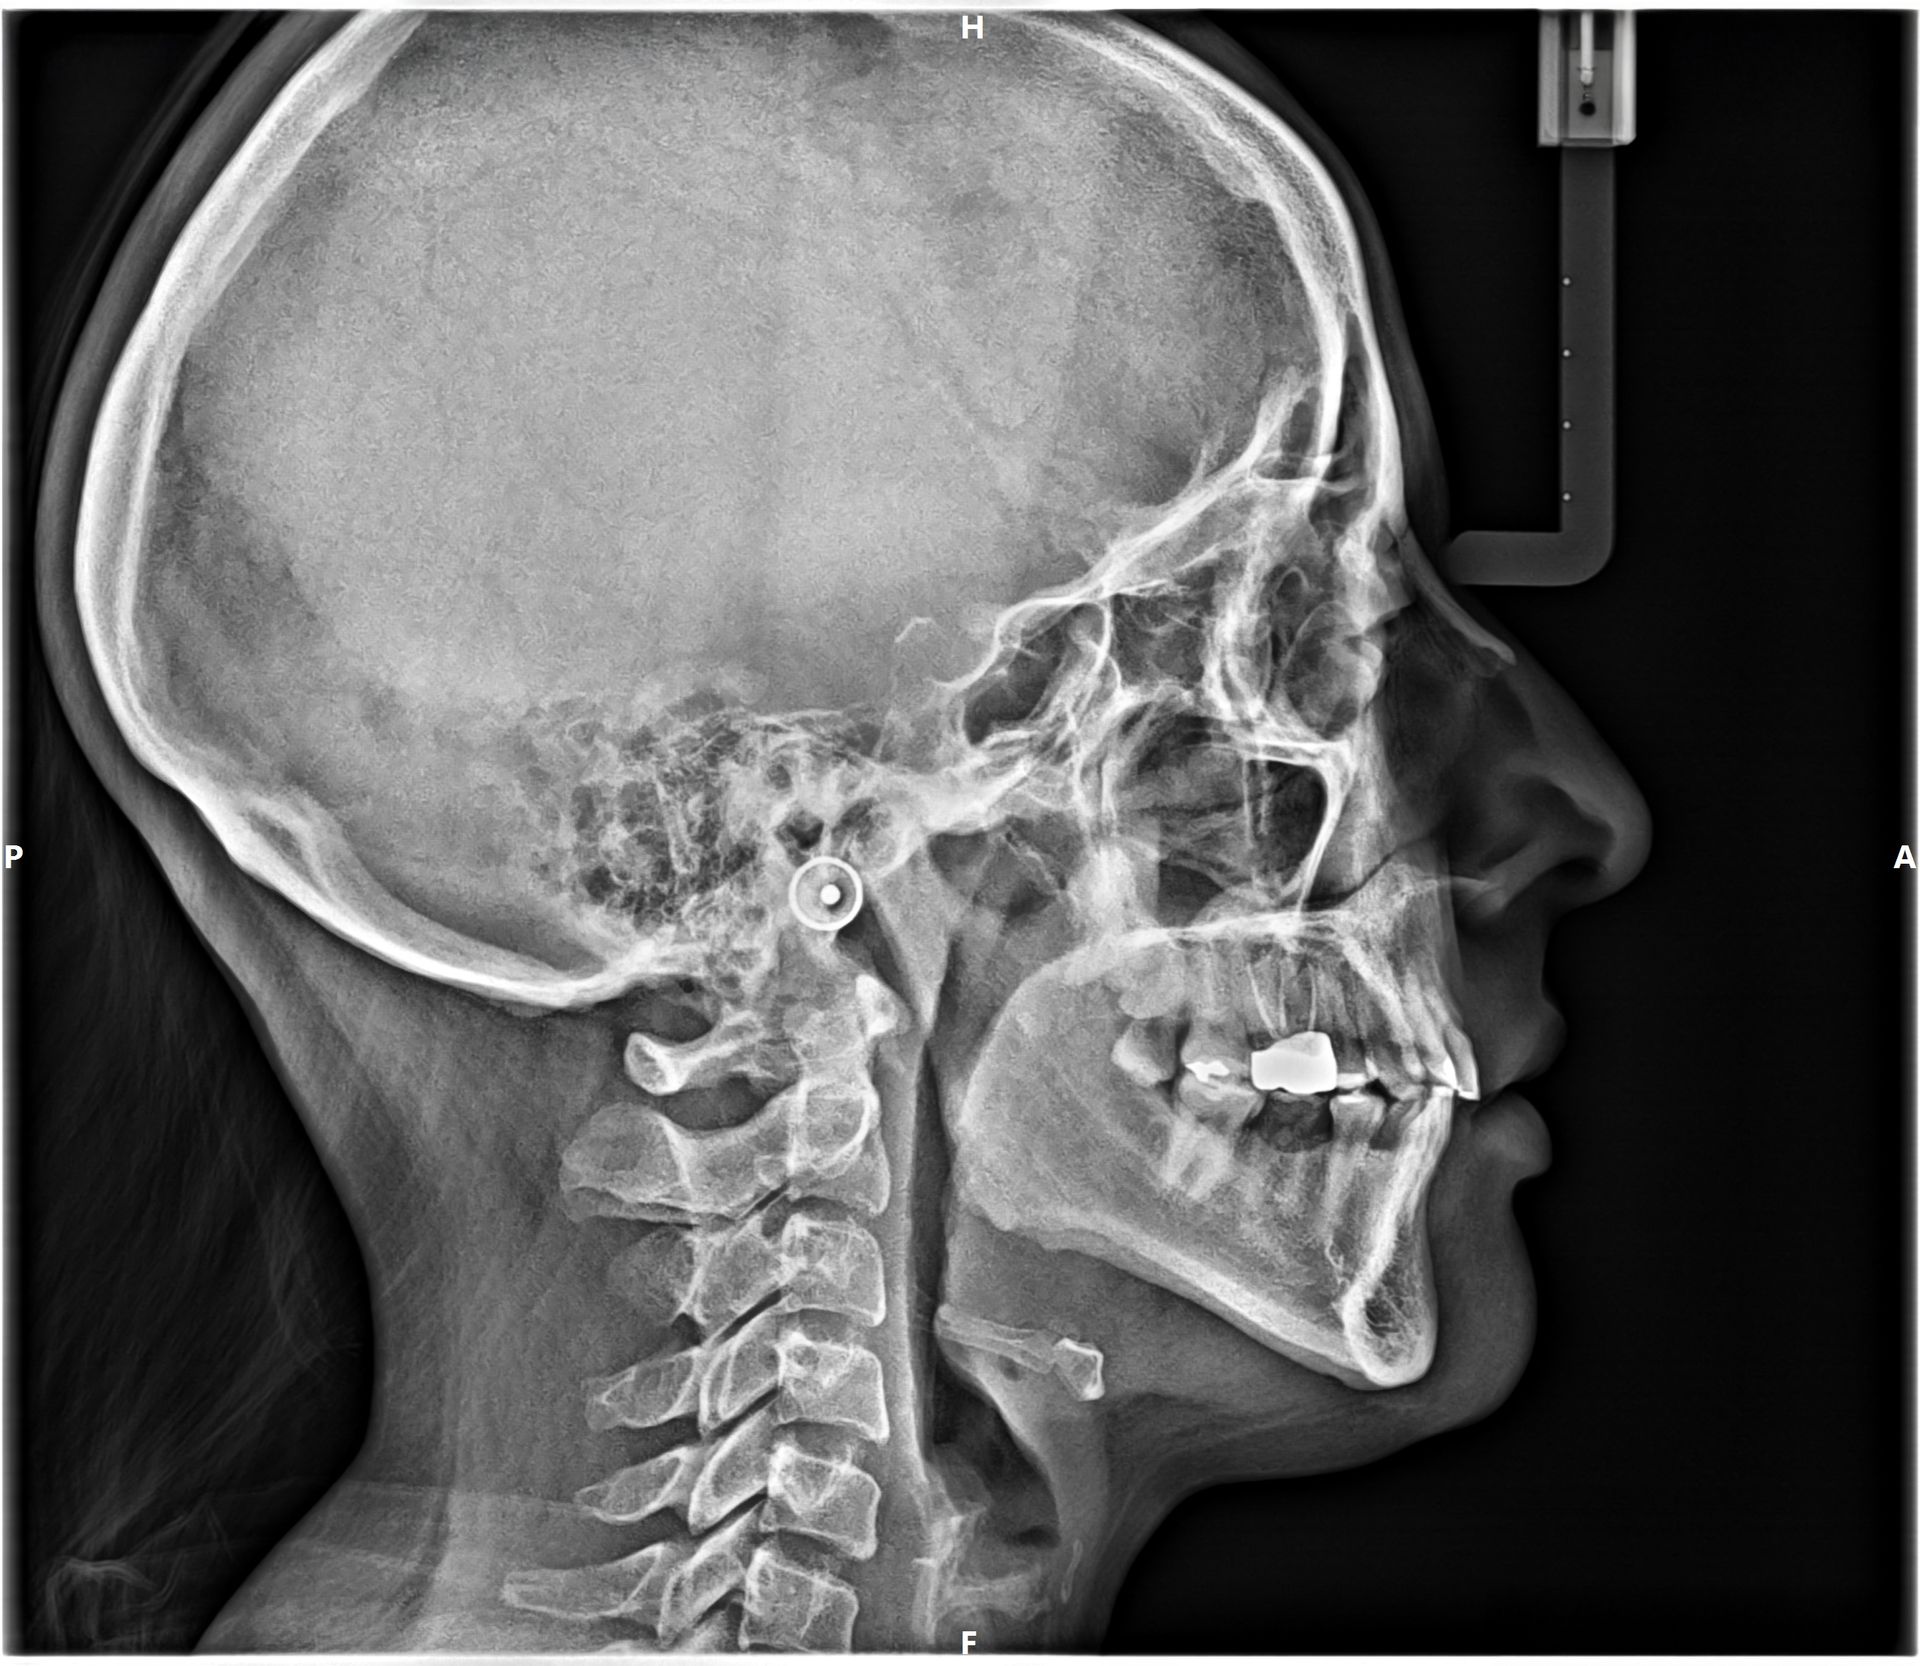

Uno de nuestros principales servicios es la adquisición de imágenes dentales 2D y 3D, fundamentales para un diagnóstico preciso y una planificación adecuada de tratamientos dentales.

Contamos con tecnología avanzada que nos permite obtener imágenes claras y detalladas de la boca y los tejidos circundantes, lo que es crucial para evaluar la salud dental y detectar posibles problemas.